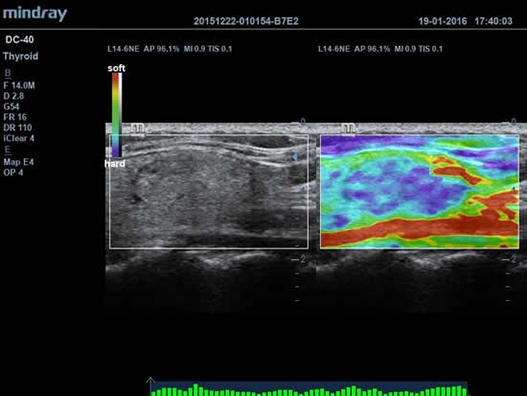

• Функция эластографии Natural Touch позволяет проводить эластографические исследования.

Natural Touch Elastography:

Да